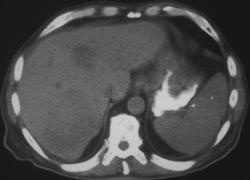

Diagnosis

Gastritis